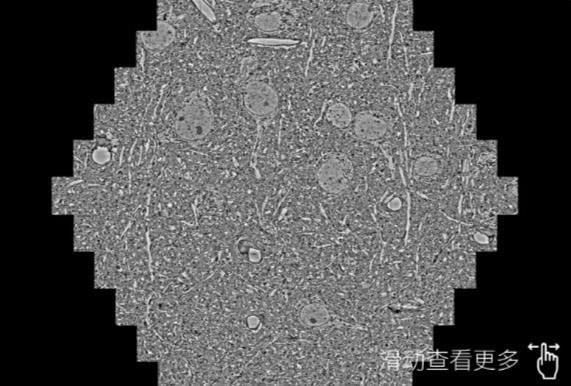

鼠脑切片。左图使用武威蔡司武威扫描电镜MultiSEM706对165μmx143pm面积区域成像,耗时仅需1.5秒。右图为鼠脑切片中30μm区域放大效果。样品由芝加哥大学B.Kasthuri提供。

使用蔡司高速武威扫描电镜MultiSEM对1mm²人脑皮层组织进行高分辨成像,并对其中的各种细胞结构进行三维重构分析。左图展示了2x3mm²组织平面中锥体神经元的三维重构效果。右图显示了局部体积神经元三维重构。图像由哈佛大学chtman实验室提供,渲染图由D. Berger 制作。